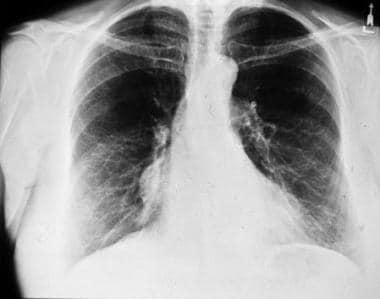

(2)正常胸腺影有时需要与胸腺囊肿、淋巴瘤、胸腺瘤、畸胎瘤及胸腺脂肪瘤等加以鉴别。如下图9、10所示。

图9示:一个分叶状胸腺淋巴瘤.(图片来自Medscape)

图10示:位于右心缘的胸腺瘤. (图片来自Medscape)

当X线不能明确诊断正常胸腺影时,及时行CT、MRI检查,结合年龄、临床表现可进行鉴别。